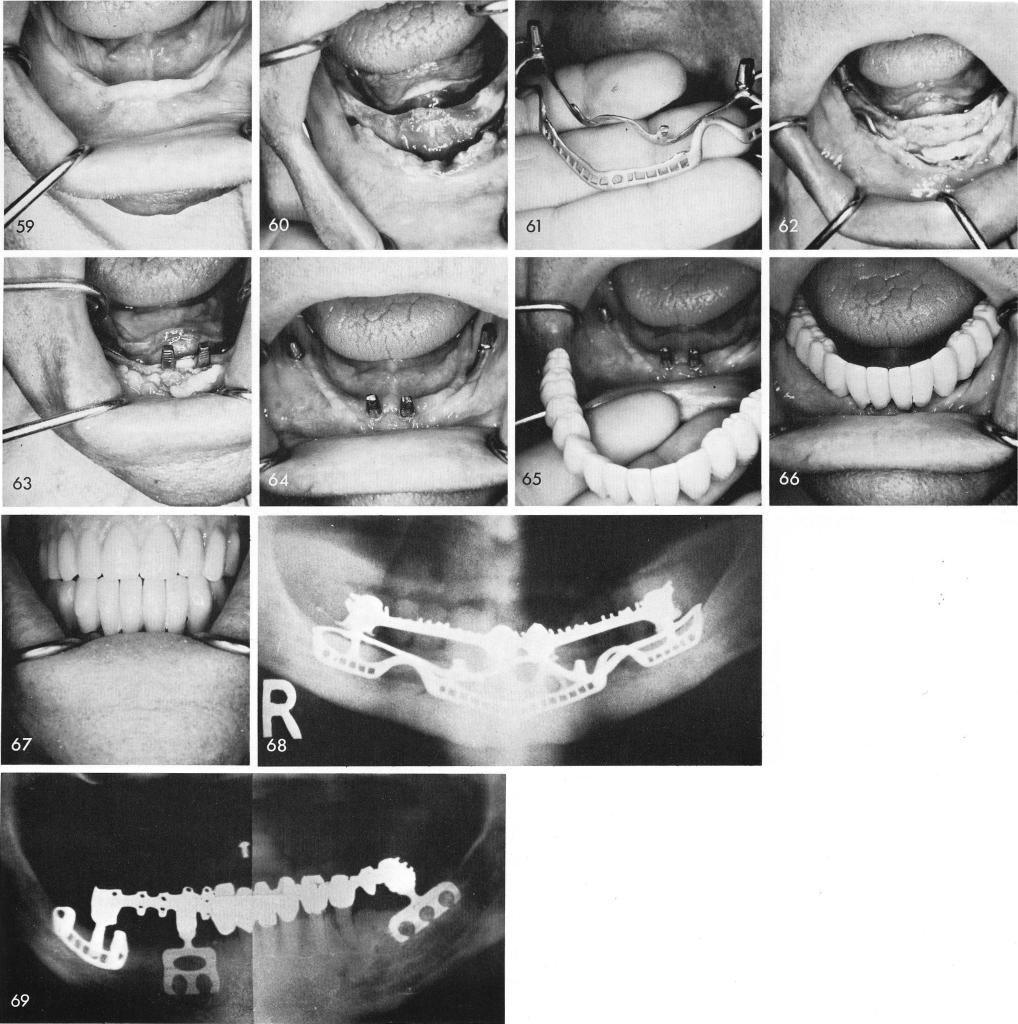

Sometimes also, in a totally edentulous mandible, fig. 59, prepared for a full subperiosteal implant, fig. 60, because of a poor fit anteriorly, those struts were removed from the implant, fig. 61. The implant still in one piece fitting around the arch does not lose any of its overall retention, fig. 62. To give necessary support for the fixed bridge a double posted blade is inserted anteriorly, fig. 63. After healing of the soft tissues, fig. 64, the completed prosthesis is ready for cementation, figs. 65, 66, 67. A final x-ray, fig. 68.

Fig. 69 shows a combination of natural teeth, blades and a uni-lateral subperiosteal implant.